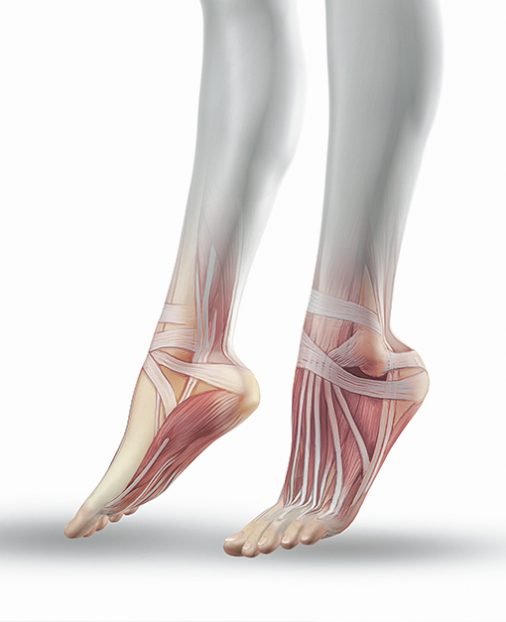

Зовнішня архітектура стопи складається зі склепінь. Вони здатні розтягуватись під впливом навантаження й повертатись у вихідний стан завдяки своїм особливостям. Склепіння стопи підтримуються м’язами та зв’язками. При їхньому ослабленні стопа втрачає правильну будову, що часто супроводжується больовими відчуттями.

Нефункціональна стопа погіршує якість життя. Важливо розуміти, що патологія стопи — це результат напружень різних м’язових груп, а не одного ізольованого м’яза. Комплексні зміни в архітектоніці стопи призводять до зміщення кісток гомілкового, колінного та кульшового суглобів. А це може стати причиною порушення постави зі зміною положення сегментів тіла. При цьому можливі наступні наслідки:

Взаємодія кісткових та м’язових компонентів стопи

Тобто стан і положення стопи впливають на постуральну й динамічну стабільність постави. А це у свою чергу впливає на якість руху й роботи травної, дихальної та серцево-судинної систем організму. Тож стан і положення стопи впливають на якість повсякденного життя. Однак кожен випадок патології стопи вимагає індивідуального підходу.

Слабкість м’язів стопи та гомілки як частковий прояв загальної функціональної слабкості організму призводить до:

Вправи на відновлення біомеханіки кроку допоможуть правильно розподілити вагу по стопі, що позитивно вплине на її функціональність. Завдяки вправам м’язи стопи зміцнюються, що забезпечує коректне розташування кісток.